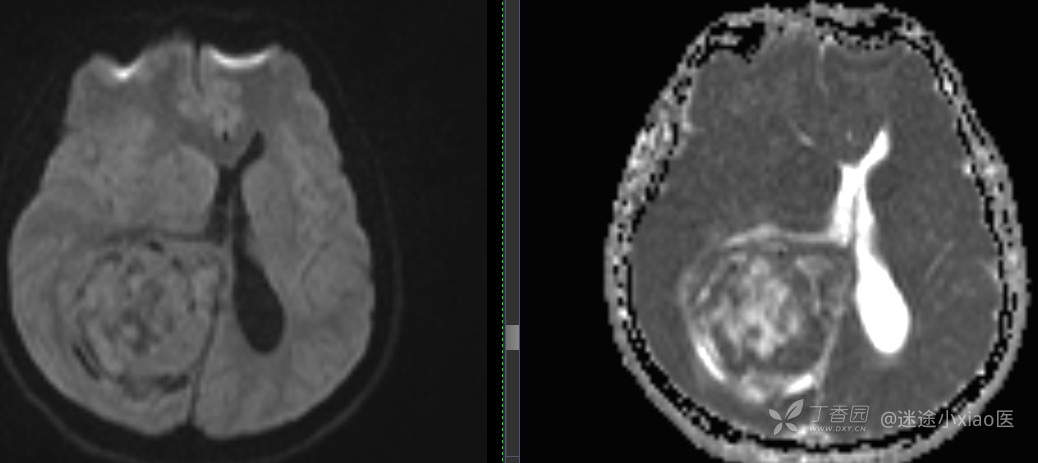

患者年龄:43

患者性别:男

简要病史:头痛3月余,查体无殊